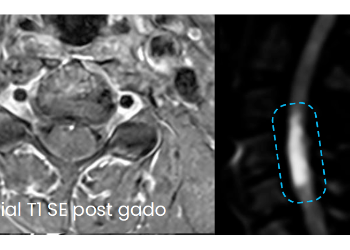

Cas clinique : Une localisation peu banale.

Présentation du cas clinique

Quel est votre diagnostic ?

Conclusions